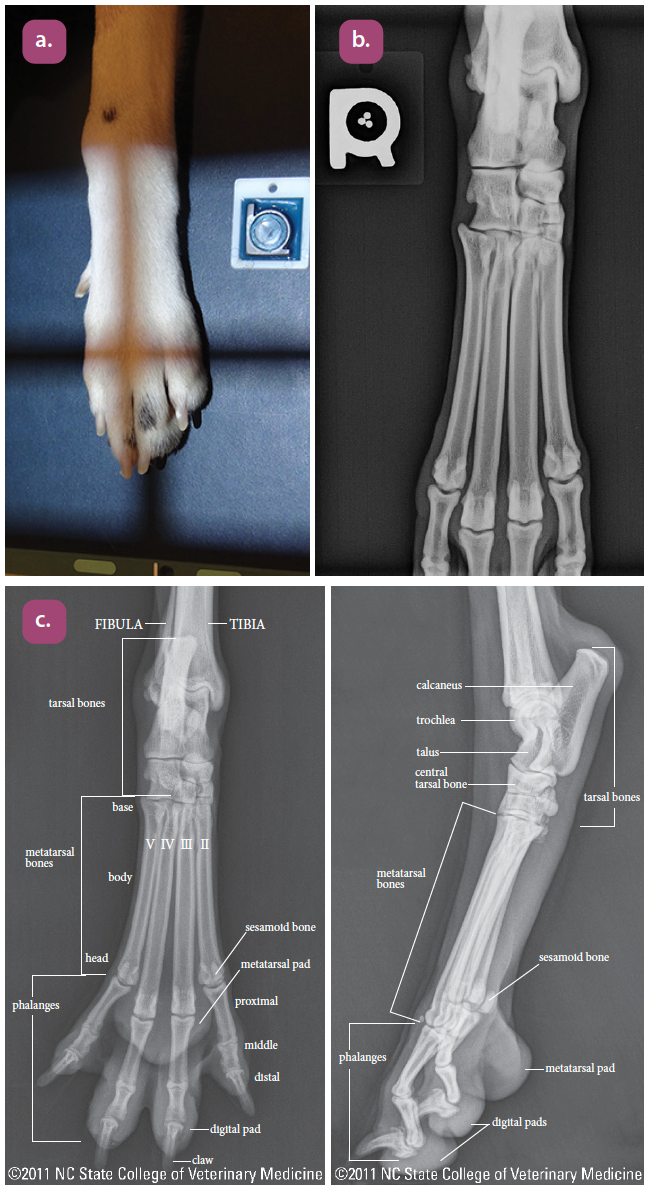

dorsoplantar projection of the tarsus

dorsoplantar projection of the metatarsus

dorsopalmar projection of the digits

lateral projection of the digits